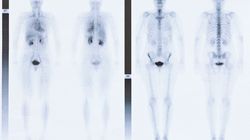

Rozpoznanie Ca jajnika, ca endometrium. Stan po histerktomii radykalnej 2014. WZNOWY 2014-2016 LECZONE CHTH. PROBLEM kliniczny Podejrzenie wznowi w kikucie pochwy. Sposób wykonania badania akwizycji przeprowadzono po 65 minutach od podania 280 MBq 18F-fug na stole włókna węglowego do planowania radioterapii bezmjodowego środka kontrastowego i.v.Glikemia przy podaniu radioznacznika wynosiła 89mg/dł GLOWA I SZYJA wzmożony wychwyt FUG w obrebie węzła chlonnego szyi w gr. IV po stronie lewej o śr. 11mm i suv max=8,5 po za tym nie wezle chlonne szyjne nie powiekszone, bez wzmożonego metabolizmu 18-F-FDG. Stan po strumektomii. tarczyca bez ognisk patoligcznego gromadzenia 18F-fug KLATKA PIERSIOWA BEZ cech powiekszonych aktywnych metaboliczne węzłów chłonnych w obrebie srodpiersia i wnęk płucnych .Płuca bez ognisk patologicznego gromadzenia FDG. Skutki bez ognisk patologicznego gromadzenia FDG. Węzły chłonne pachwowe niepowiekszone. JAMA BRZUSZNA I MIEDNICA wzmożony wychwyt FDG w obrebie Licznych hipoodensyjnych w CT OGNISK W wątrobie, zlewajace się ze sobą obecne we wszystkich segmentach wątroby. Największe zmiany w seg 7 i 5 o łącznym wymiarze 73×44 mm i suv max=15,1. Wątroba z wydłużonym paktem lewym sięgający powłok lewego nadbrzusza odmiana anatomiczny normy.W lewym płacie w obrebie lewego nadbrzusza zmiana ogniskowa uwypuklajaca zarys płata o sr. 26mmm i suv max=9,7. Węzłów chłonnych w nadbrzusza w obrebie wnęki wątroby przy głowie trzustki suv max=8,4 śr do 15mm Węzłów chłonnych przyaortalnych obustronnie o wym do 15×11mm i suv max =10,7 pomiar na wysokości naczyń nerkowych po stronie prawej Węzłów chlonnychnw krezce jelita cienkiego o sr. do 10mm i suv max=5,3 nieregularnych zmian naukowych kikuta pochwy i ściany pecherza moczowego.dwa zlewajace sie obszary w kikucie pochwy o łącznym wymiarze ok 32×33mm i suv max=9,6 . Kolejna zmiana słabo wyodrebnia sie przy pęcherza moczowym (ze względu na wysoką fizjologiczna aktywność moczu) odcinkowy pogrubiala ściana pecherza moczowego pomiar suv niewiarygodny (aktywność moczu). Węzła chlonnego w okolicy przedkzywozej po stronie lewej o sr. 8mm i suv max=4,7 położony po stronie lewej odbytnicy na wysokości trzonu S3. Bez ognisk patologicznego metabolizmu 18f-fdg w obrebiensledziony nadnerczy i trzustki, sledziona niepowiekszone.fizjologiczne wydalanie radioznacznika z moczem fizjologiczne wydzielanie radioznacznika do pętli jelitowych Uklad kostny: bez ognisk patologicznego metabolizmu 18f-fug dla procesu rozrostowego. W tej chwili mama przyjmuje chemioterapia korboplatyne . Jakie są rokowania czy chemia będzie skuteczna? Proszę o interpretacje wynikow